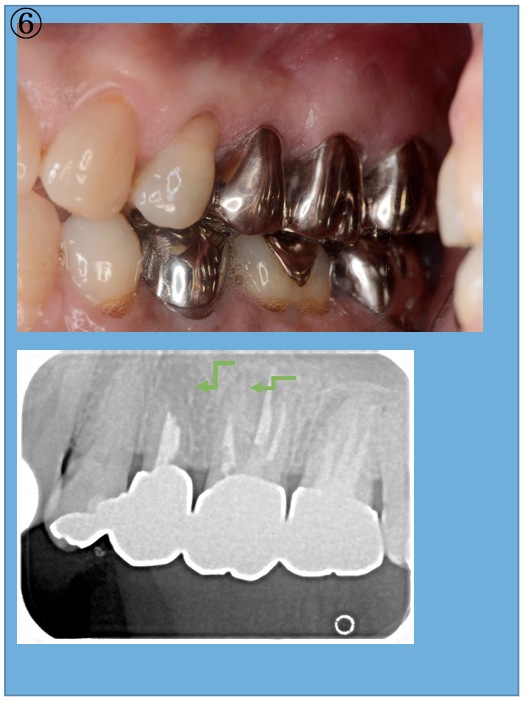

深い虫歯と根の病気 CATEGORY 症例集 DATETIME2015年01月19日 AUTHORmaruyama-park2016 当初、歯を抜くことも検討したが部分矯正と外科処置で対応していい経過を辿っている症例 ①深い虫歯と根の病気があります。 ②虫歯を取り除き根の治療を行いました。 ③虫歯が深いため、矯正治療で歯茎の中に埋まっている健全な歯を引きだしています。 ④2か月ほどかけて適切な位置まで歯を引き出しました。 ⑤その後外科処置で歯茎の位置の調節と根にできた病気の掻把(除去)行いました ⑥冠を被せて二年後、根の先の病気は治癒し安定した経過を辿っています。 保存が困難な深い虫歯の治療~部分矯正治療を行い歯牙の保存を行いました。 > 最近の投稿 前歯の歯周治療の流れ (16/07/29) やせてしまった歯茎の再生治療 (16/07/29) 三年の治療期間を経て・・・。 (16/07/28) 保存が困難な深い虫歯の治療~部分矯正治療を行い歯牙の保存を行いました。 (15/06/19) 深い虫歯と根の病気 (15/01/19) カテゴリー 症例集 (1) アーカイブ 2016年7月 (3) 2015年6月 (1) 2015年1月 (1) 診療時間・休診日 月・水曜日 火・金・土曜日 昼休み 木曜日 日・祝日 AM9:30~PM8:30 AM9:30~PM6:00 AM12:30~PM2:00 インプラント手術日 休診 ※祝祭日を含む週の木曜は平日どおり診療しております。 治療紹介TREATMENT 歯周病治療 歯周病外科治療 インプラント 顕微鏡歯科治療 一般歯科治療 部分矯正治療 入れ歯治療 診療時間・休診日 月・水曜日 AM9:30~PM8:30 火・金・土曜日 AM9:30~PM6:00 昼休み AM12:30~PM2:00 木曜日 インプラント手術日 日・祝日 休診 ※祝祭日を含む週の木曜は平日どおり診療しております。 症例紹介Case 料金表Price List 治療の流れCase 症例紹介Case 料金表Price List 治療の流れCase